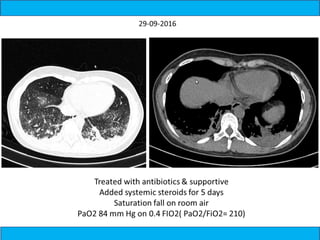

A medical document discusses hypoxia following a road traffic accident. It describes four types of pulmonary contusion caused by direct chest compression, shearing against vertebral bodies, fractured ribs directly injuring the lung, or tearing of lung parenchyma due to prior adhesions. The document also mentions management of pulmonary contusion.